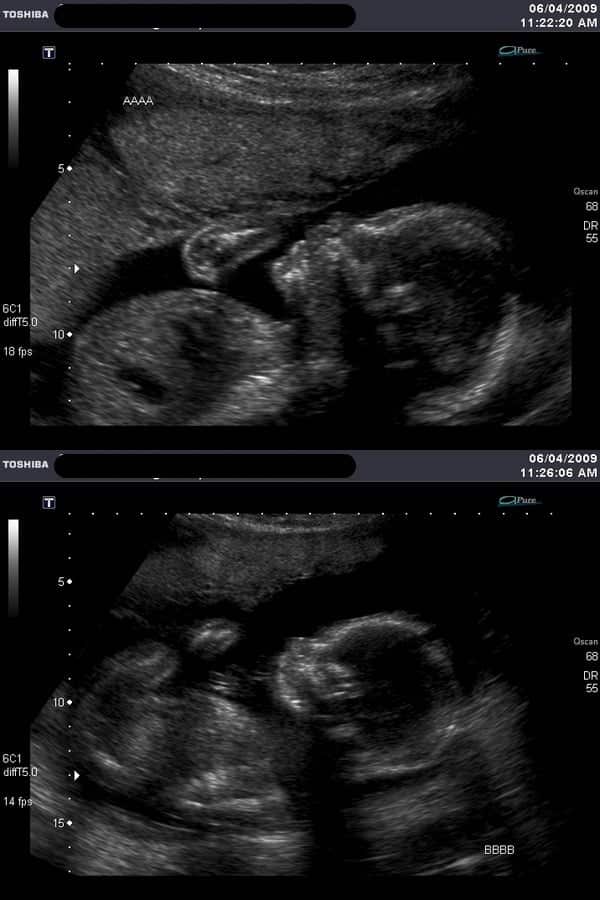

Ultrasound Photos at 30 Weeks Pregnant With Twins